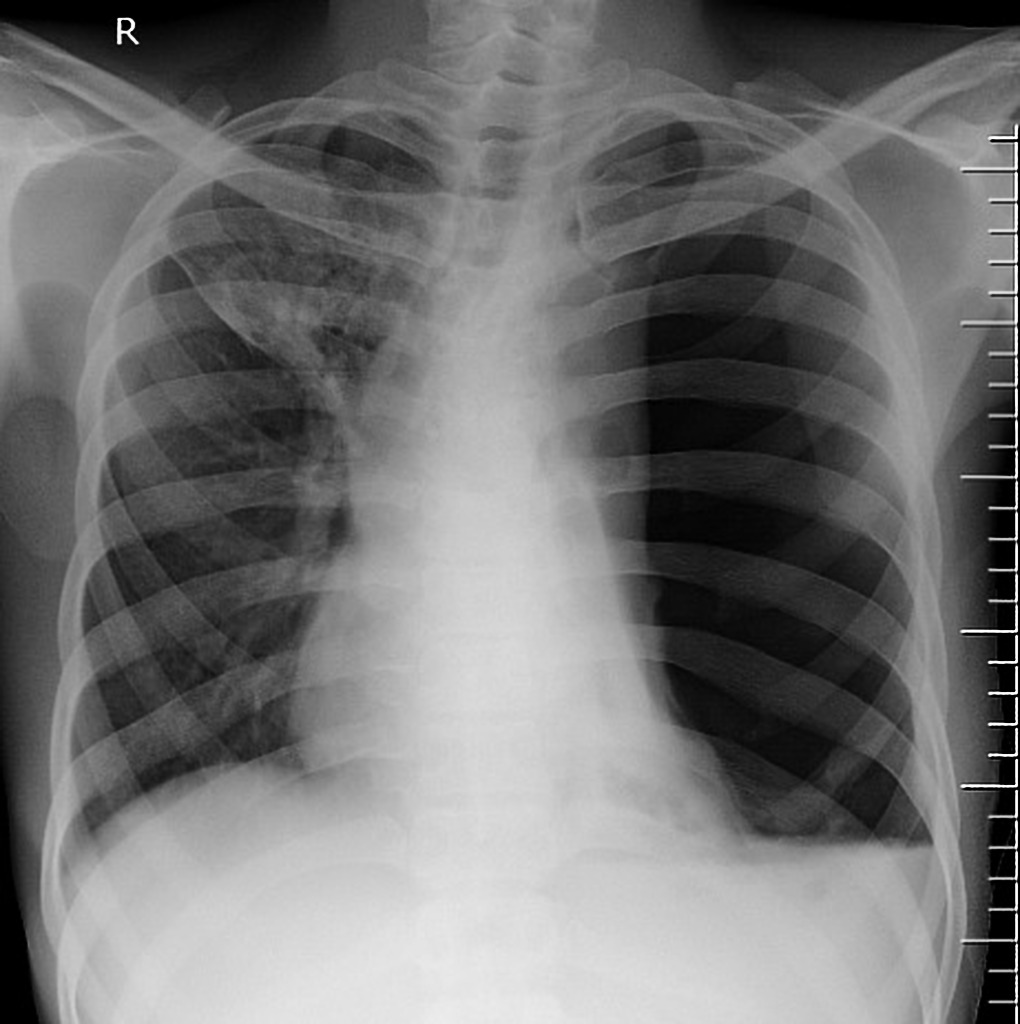

Hydropneumothorax